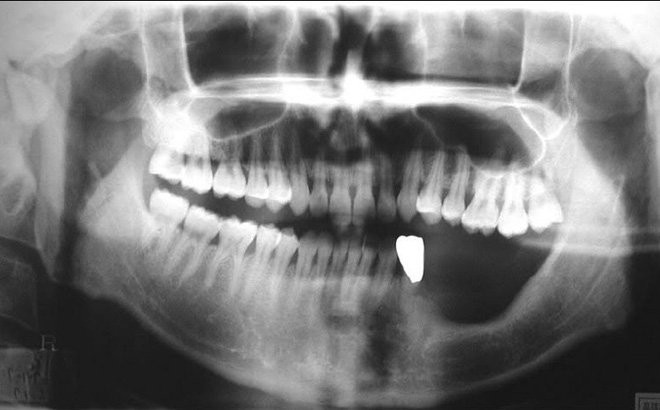

Hình ảnh chụp hàm răng của nam thanh niên khiến anh vô cùng tiếc nuối và sợ hãi.

Hàm răng của nam thanh niên đã bị viêm tủy xương, phải diệt tủy điều trị, phòng tránh va đập hàm suốt đời.